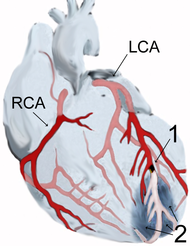

Depending on the location of the obstruction in the coronary circulation, different zones of the heart can become injured. Using the anatomical terms of location corresponding to areas perfused by major coronary arteries, one can describe anterior, inferior, lateral, apical, septal, posterior, and right-ventricular infarctions (and combinations, such as anteroinferior, anterolateral, and so on). For example, an occlusion of the left anterior descending coronary artery(LAD) will result in an anterior wall myocardial infarct. Infarcts of the lateral wall are caused by occlusion of the left circumflex coronary artery(LCx) or its oblique marginal branches (or even large diagonal branches from the LAD.) Both inferior wall and posterior wall infarctions may be caused by occlusion of either the right coronary artery or the left circumflex artery, depending on which feeds the posterior descending artery. Right ventricular wall infarcts are also caused by right coronary artery occlusion.